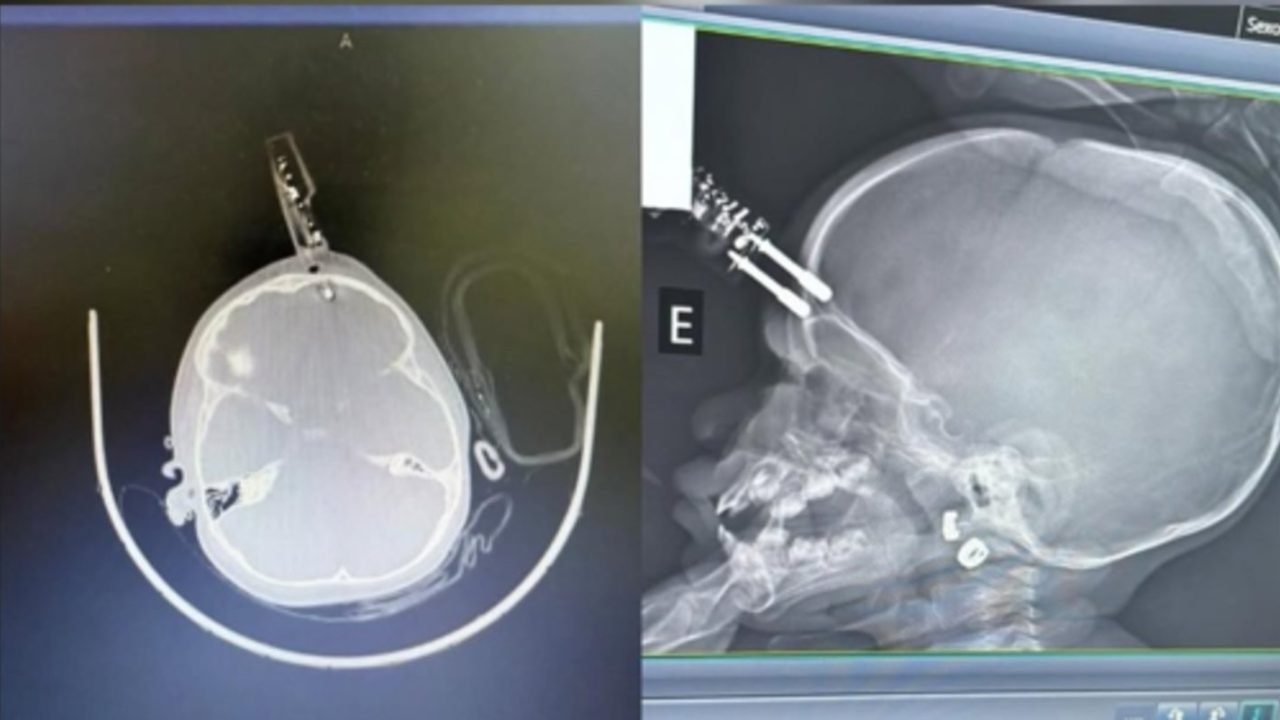

Menina de 1 ano se acidentou após cair da cama enquanto a mãe estava no banheiro